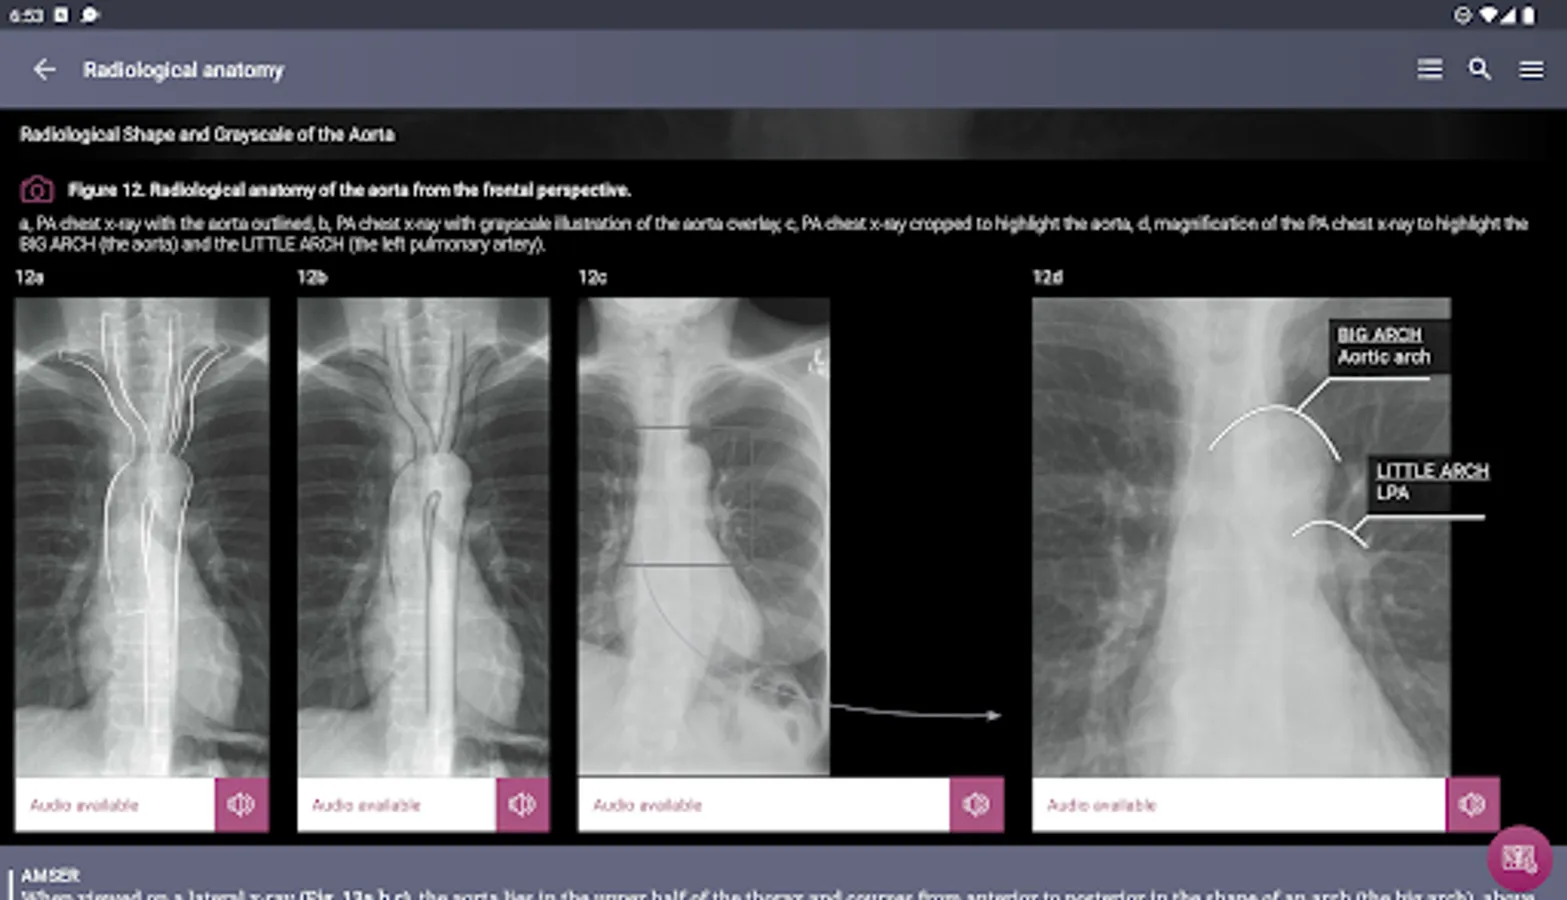

Radiological Anatomy – Descriptions of various anatomical structures as they would appear on PA and lateral chest x-rays.